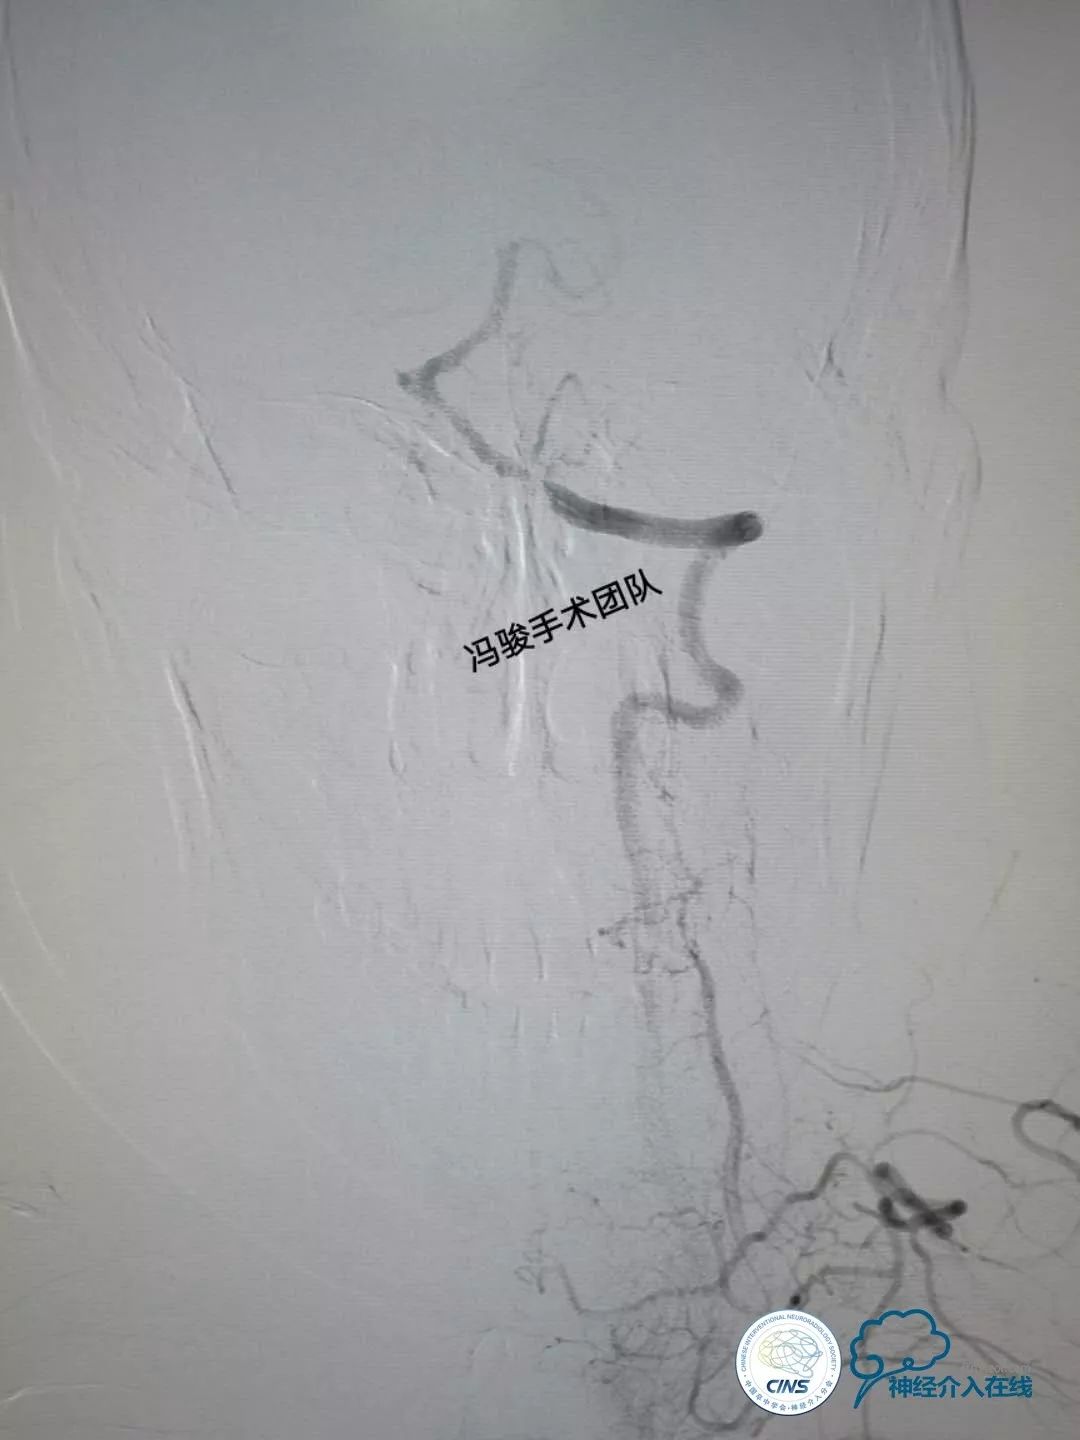

DSA显示,患者右椎动脉发育不良,V2段远端闭塞,仅存的左椎动脉串联病变,V1段迂曲,V4段99%狭窄(并局部溃疡),且病变处发出左小脑后下动脉(PICA),PICA亦99%狭窄,可谓“命悬一线”!

患者53岁,有脑干梗死史,反复晕厥发作,处理孤独左椎动脉V4段99%狭窄,患者获益最大!但此处支架极可能压闭PICA,即刻导致小脑梗死!

如果同时解决左椎动脉V4段+PICA,需要较高的处理颅内分叉病变的手术技巧!如履薄冰!该如何操作?